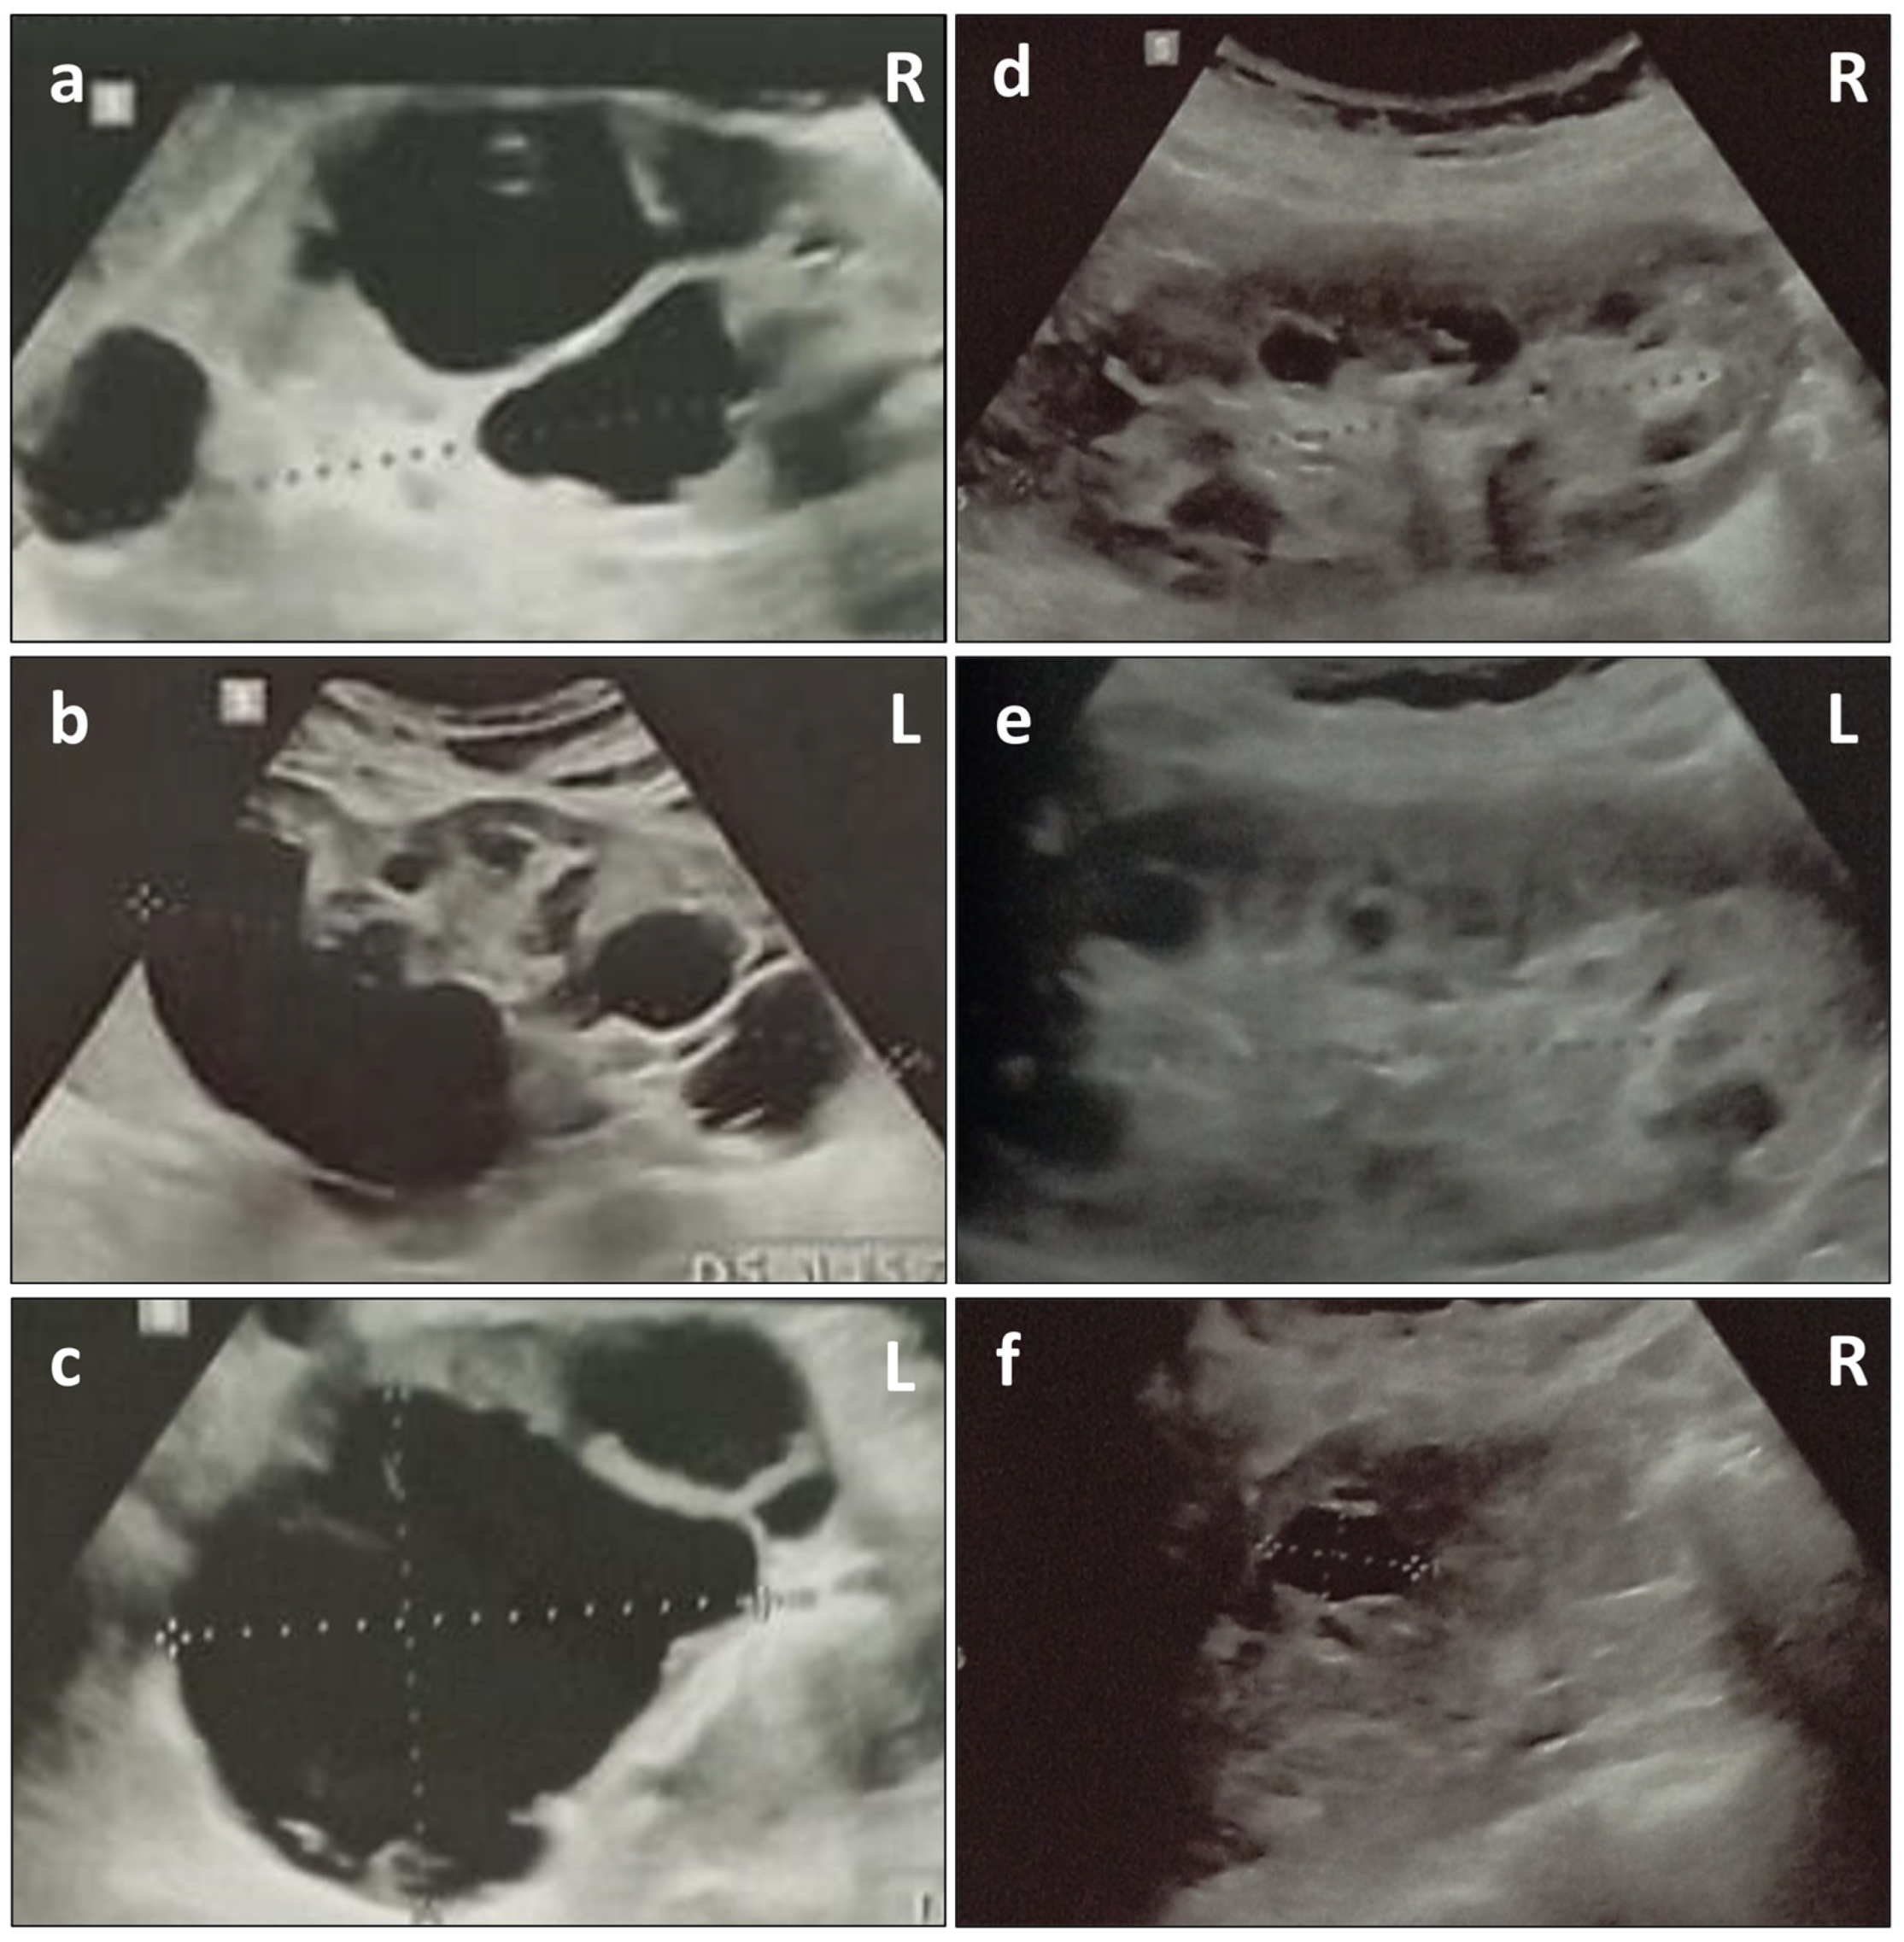

2. Case Presentation